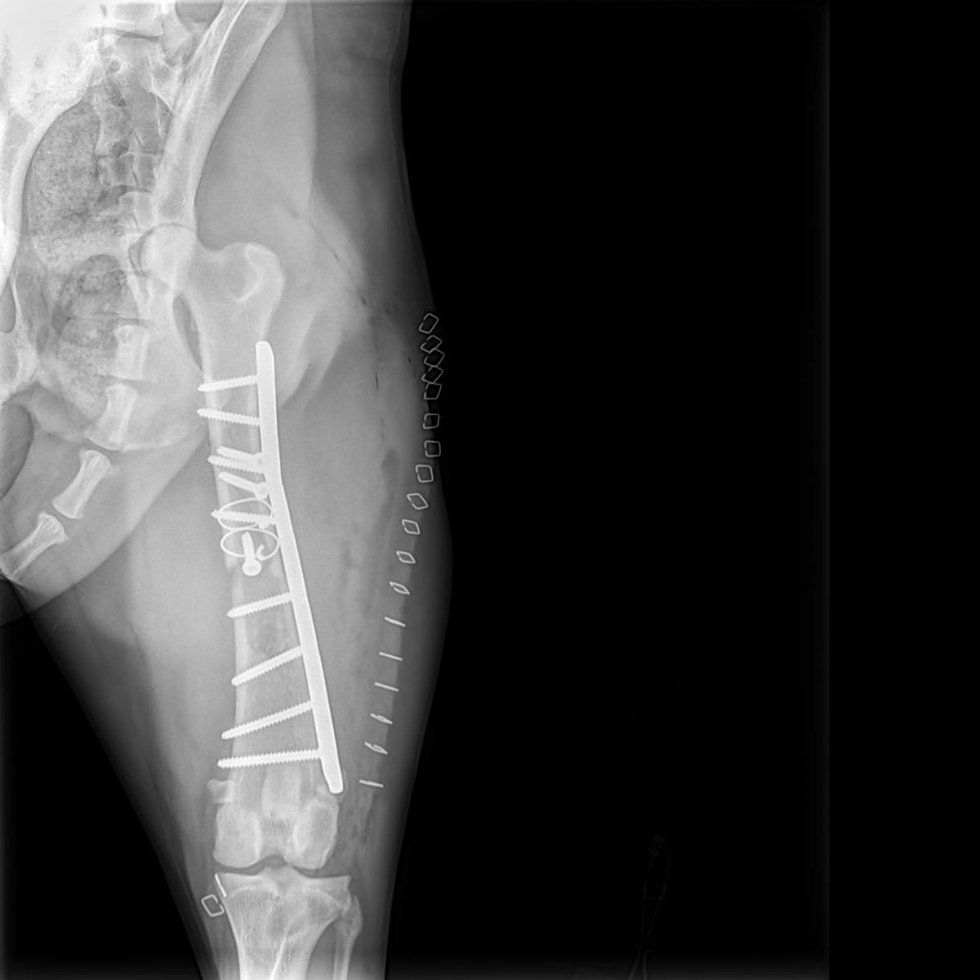

Traumatologia ortopedica

Fratture alle gambe sono il problema più comune ortopedico presentato presso la nostra clinica e di solito il risultato di un incidente stradale.

-

Frattura del bacino sono una delle lesioni più comuni in traumatologia veterinaria, di solito causata da un grave incidente trauma come incidenti di macchina. Le fratture pelviche di solito comportano una o piu fratture delle ossa pelvicheche potrebbero richiedere perni o piastre ossee.Rotture sui lati sinistro e destro e crollo di un segmento osseo che causano il restringimento del bacino.

Placche ossee sono uno dei più forti e più efficaci metodi di fissazione di una frattura. Esse contrastano le forze di compressione, torsione e forze di trazione. Una placca ossea un pezzo in acciaio con fori per viti che stabilizzano la placca all'osso.

chiodo bloccato .Questa è una procedura in cui un grande "pin" viene modificato per accettare viti di bloccaggio attraverso l'osso e sia sopra che sotto la frattura. Questo fornisce una fissazione molto sicura con invasione tissutale minima.